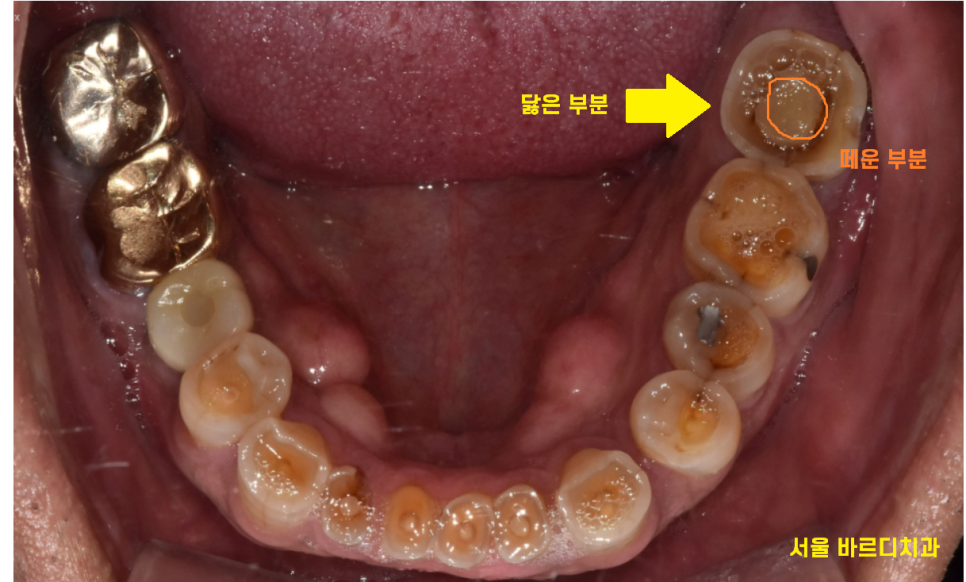

23.10.10

환자분께서는 신경치료 후 보철을 원하지 않으셨습니다.

그래서 신경치료를 위해 뚫어둔

구멍만을 메꿔서 치료를 마무리 해드렸습니다

환자분께는

신경치료 후 보철을 하지 않으면 발생할

문제점에 대하여 충분히 설명을 드렸습니다.

환자분 , 보철을 해주는 것은 치아를 보호하기 위해서입니다.

단단한 힘을 받게되면

치아가 금이가거나 부러질 수 있어요.

단단한 음식은 반드시 피해주세요!!